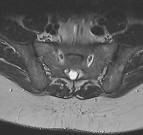

MRT – auch Kernspintomografie, oder Magnetresonanztomografie genannt – ist eine diagnostische Technik zur Darstellung der inneren Organe des menschlichen Körpers. Hier haben wir ein paar Bilder, um zu zeigen wie solche Aufnahmen mit dieser Technik aussehen.

Die Bilder sind nicht für diagnostische Zwecke geeignet!